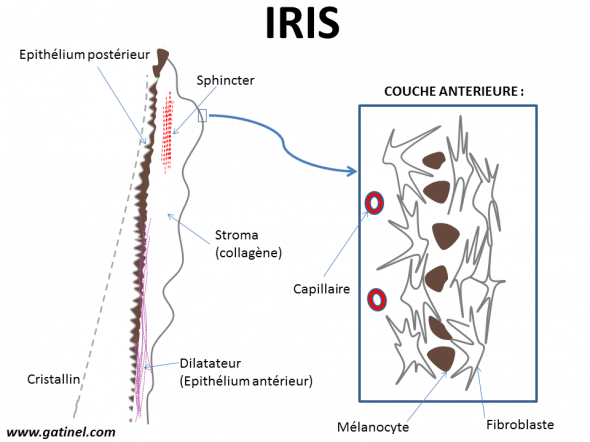

Description histologique simplifiée de l’iris. La couche antérieure est formée d’une matrice collagène où s’enchevêtre les fibroblastes, et des cellules pigmentées (mélanocytes) situées un peu plus en profondeur. Les yeux marrons, noisette et verts possèdent une proportion variable de ces cellules, dont sont dépourvus les yeux bleus.

Cette fine couche est une extension de la couche stromale : elle est la plus superficielle, et c’est elle qui donne son aspect et sa couleur à l’iris. Elle est composée de diverses cellules : les fibroblastes (qui fabriquent le collagène), des mélanocytes (qui contiennent du pigment). Ces cellules sont insérées dans une trame de fibrilles de collagènes. Les fibres de collagènes ont une orientation plutôt radiaire. Les fibroblastes ont une forme particulière : ces cellules forment de nombreuses interconnexions, qui sont en partie responsables des fines variations du relief cornéen (avec une alternance de petites saillies et de creux ou cryptes), et qui se distribuent de matière aléatoire. Ces structures jouent aussi un rôle dans la couleur apparente de l’iris, car elles provoquent une diffusion de la lumière visible, plus marquée dans les courtes longueurs d’onde (bleu). La densité du réseau formé par les expansions des fibroblastes varie d’un œil à l’autre.

Sous la couche la plus superficielle des fibroblastes, se situent les cellules mélanocytaires. Quand elles se groupent en amas, elles forment des petits bourrelets pigmentés comparables à des neavi.